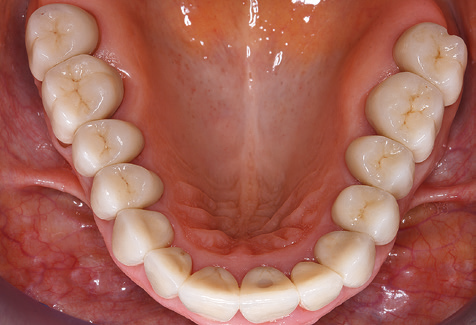

Eine 52­-jährige Patientin stellte sich nach Zahnverlust im 3. Quadranten erstmals 2004 vor. Sie hatte den Wunsch nach einer prothetischen Neuversorgung. Im Rahmen der parodontologischen und radiologischen Diagnostik zeigte sich ein ausgeprägter parodontologischer Behandlungsbedarf. Die Zähne 48, 28, 27 zeigten zudem eine infauste Prognose und wurden entfernt (Abb. 1). Nach der erfolgreich abgeschlossenen systematischen PAR­Therapie wurde eine festsitzende implantatprothetische Versorgung mit Insertion von fünf Implantaten in Regio 35, 36, 37 und 46, 47 durchgeführt. Die prothetische Versorgung der natürlichen Zähne erfolgte mit verblendeten Zirkonoxidkeramikkronen, die Implantate wurden mit zweiteiligen individuellen Zirkonoxidabutments und ebenfalls verblendeten Kronen aus einer Zirkonoxidkeramik versorgt (Cercon base colored, Dentsply Sirona Lab). Die definitive Insertion der prothetischen Versorgung erfolgte im Jahr 2005.

Aufgrund der bestehenden parodontalen Vorerkrankung erfolgte die unterstützende Parodontaltherapie (UPT) in den ersten Jahren in einem Drei­Monats­Intervall. Dabei zeigte die Patientin eine hohe Motivation und gute Compliance. Bei den jährlich erhobenen Sondierungsbefunden zeigten sich stabile parodontale Verhältnisse mit einem BOP­Index unter fünf Prozent. Aufgrund der stabilen parodontalen Situation und der guten Mitarbeit der Patientin wurde ab dem sechsten Jahr der prothetischen Funktionsphase das Recallintervall auf halbjährlich um­gestellt. Auch mit diesem veränderten Recallintervall zeigten sich bei der jeweils jährlichen Aufnahme des Parodontalstatus stabile parodontale Verhältnisse, ohne Zunahme der Sondierungstiefen und einem BOP­Index unter fünf Prozent (Abb. 2a und b).

Im Rahmen der Zehn­Jahres­Kontrolle zeigten sich keine Hinweise auf einen fortschreitenden parodontalen Attachmentverlust oder einen periimplantären Knochenverlust (Abb. 3).

Die Patientin befindet sich weiterhin in einem halbjährlichen Intervall für die UIT. Nachfolgend werden am Beispiel dieser Patientin die einzelnen Arbeitsschritte einer strukturierten UPT­Sitzung aufgezeigt, so wie sie nahezu unverändert über den gesamten Funktionszeitraum von immerhin zwölf Jahren durchgeführt wurden. Natürlich wurden über diesen Zeitraum einige neue Materialien und Geräte in das Konzept integriert. In diesem klinischen Fallbericht wird das aktuelle Material­ und Gerätekonzept präsentiert.